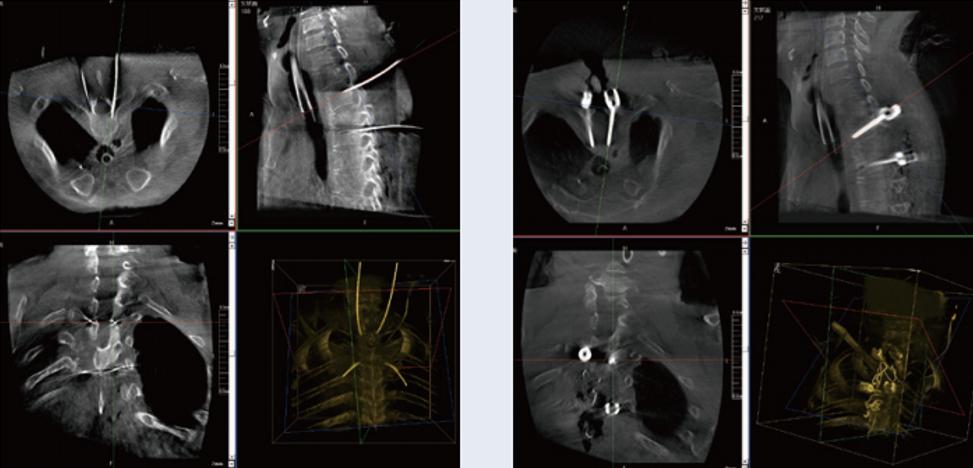

螺釘規(guī)劃后的圖像

植入螺釘后的圖像

術(shù)中三維C臂與骨科導(dǎo)航機(jī)器人配合應(yīng)用,實現(xiàn)準(zhǔn)確定位,確保了手術(shù)安全、快捷完成。術(shù)后二維、三維影像顯示手術(shù)效果良好,達(dá)到預(yù)期目的。

普愛醫(yī)療三維C臂提供了高質(zhì)量的術(shù)中實時三維圖像數(shù)據(jù),保障了骨科導(dǎo)航機(jī)器人手術(shù)的準(zhǔn)確度和安全性,取得不錯的手術(shù)效果。同時,三維C臂特有的斷層成像,能幫助醫(yī)生在術(shù)中非常直觀地判斷螺釘植入的準(zhǔn)確度。